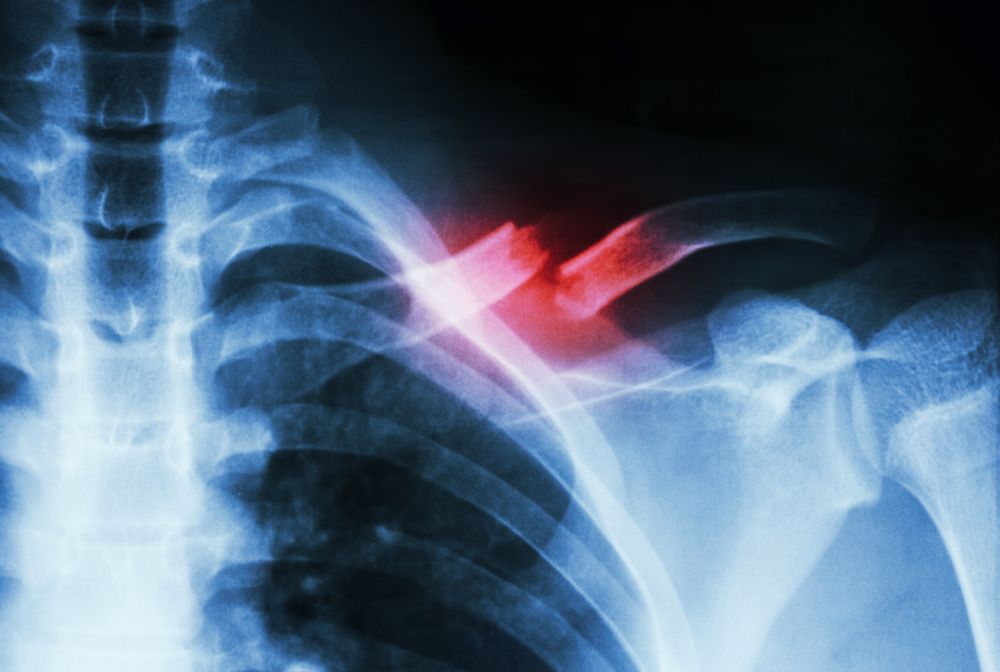

- Clavicle (collar bone)

Fractures are by definition serious injuries. They can lead to bone and joint deformities, infections, pain, blood vessel complications, nerve damage, arthritis, and other problems. This is especially a problem with the elderly and for any one who is not treated immediately. Fortunately, with the proper medical care, they usually heal completely. Therefore, it is essential that the injured person go to an emergency room and see an orthopedic surgeon who can perform x-rays and provide the medical care he or she needs.

Depending on the severity, a cast made of plaster or fiberglass is commonly applied. Most broken bones heal successfully after they are reset. Other treatment includes braces and traction. With more extreme cases, external fixation with pins or screws or open reduction and internal fixation (metal rod and nail) are employed.